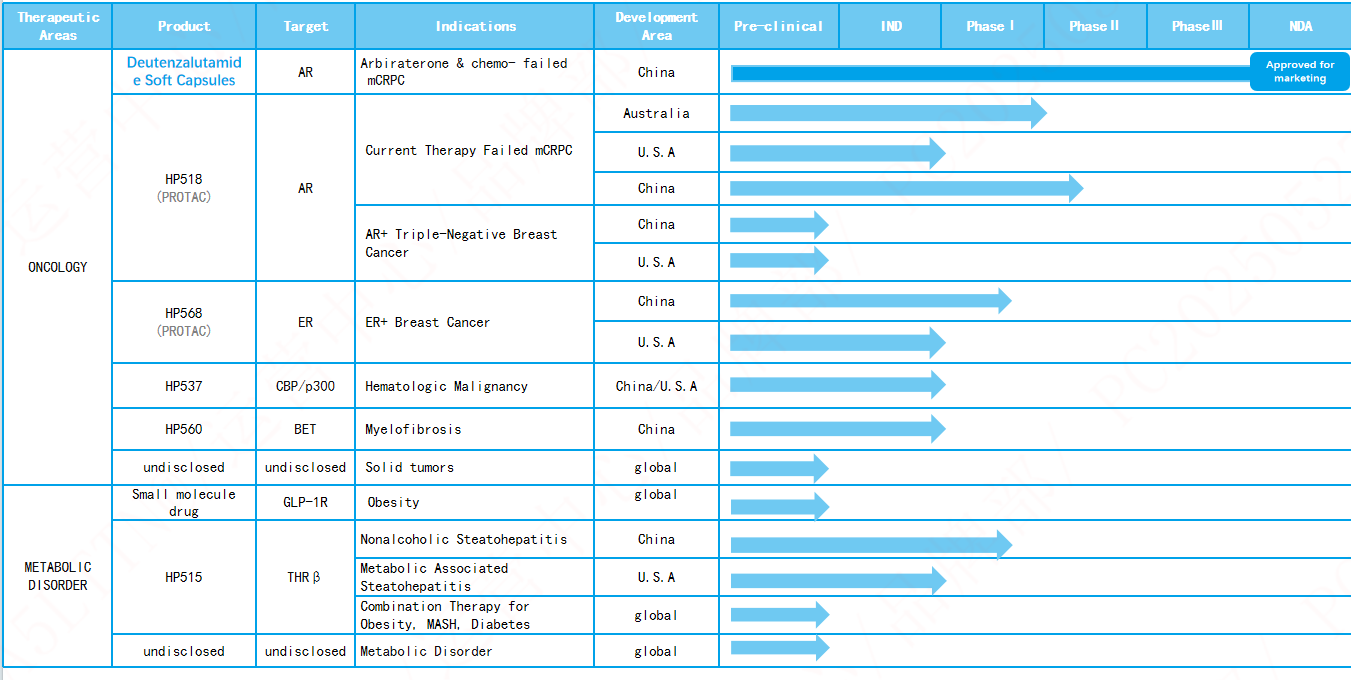

HC-1119 is the deuterated compound of enzalutamide, which is a second-generation AR antagonist. Compared to enzalutamide, HC-1119 has lower metabolic rate, higher plasma exposure, and lower brain exposure at equivalent doses in preclinical model. HC-1119 has the potential to be safer and to be used at a lower clinical dose. HC-1119 program has been adopted into National Major Projects of “Significant New Drugs Creation”. Two phase-III clinical trials are being carried out in China and globally,the NDA application of HC-1119 was accepted by NMPA in November 2023.The investigational product was approved for marketing from the NMPA in China on May 29, 2025.

HP518 is an oral PROTAC drug, with the potential to solve the drug resistance to prostate cancer due to AR variation. HP518 demonstrates good oral exposure and bioavailability in animal model. HP518 has high activity of degrading wild type AR and variant AR resistant to enzalutamide, high selectivity to AR, and excellent anticancer activity of AR-dependent prostate cancer cells. It also shows obvious effect on prostate cancer animal model. At present HP518 is in Phase I/II clinical study.